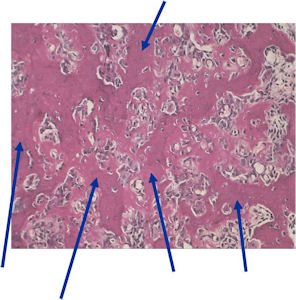

Microscopic Pathology

- The nidus of an osteoid osteoma consists of vascularized fibrovascular stroma and trabeculae of immature woven bone

- Nidus is sharply demarcated from surrounding reactive bone and there is an abrupt zone of transition between normal bone and the osteoid osteoma. There is no permeation of the lesion through the surrounding reactive trabeculae of bone,

- The trabeculae are uniformly lined by plump, uniform, active osteoblasts (“Osteoblastic Rimming)

- Osteoclasts may be prominent

- Mature nidus consists of more heavily calcified trabeculae of woven bone and osteoid

- No abnormal mitoses